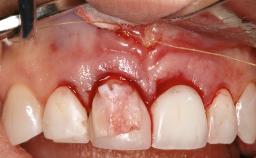

In this case, Myroslav Solonko, Ignacio Sanz Sánchez and Mariano Sanz present a treatment that aims to eliminate exposed implant threads by modifying the implant surface, converting a moderately-rough surface into a smooth surface.

A 63-year-old male patient was referred to the post-graduate periodontal clinic of the Complutense University of Madrid for the treatment of peri-implantitis. According to the patient’s record, all his maxillary teeth had been extracted ten years previously due to severe periodontitis, and a full-mouth implant-supported restoration on eight implants was placed. No supportive periodontal therapy was provided apart from occasional check-ups by the restorative dentist.